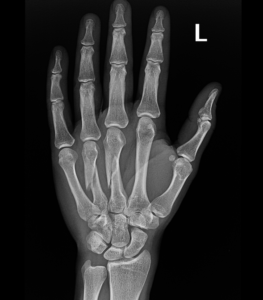

- Hand Fractures.

- Open or compound fracture – the skin overlying the fracture is also broken. Displaced or nondisplaced fracture – treatment options depend on whatever the broken bone is displaced or nondisplaced

if the fracture is displaced, surgery may be needed to put the bone back into the correct position and fix the bone with Plates & screws or nails for adequate healing to occur.